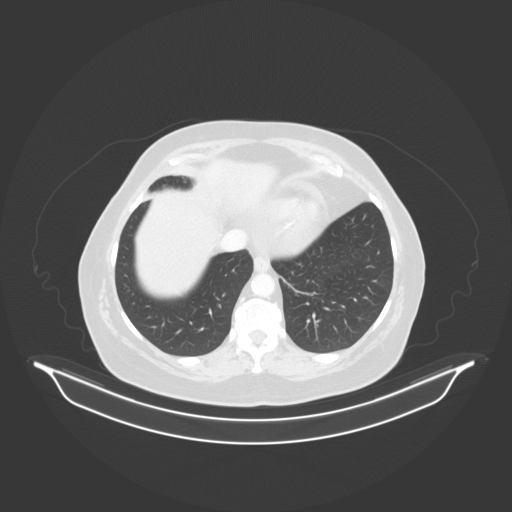

Generated VENOUS CT scan (A→B translation)

Lung window (WL -600, WW 1500 β†’ Low βˆ’1350, High +150)